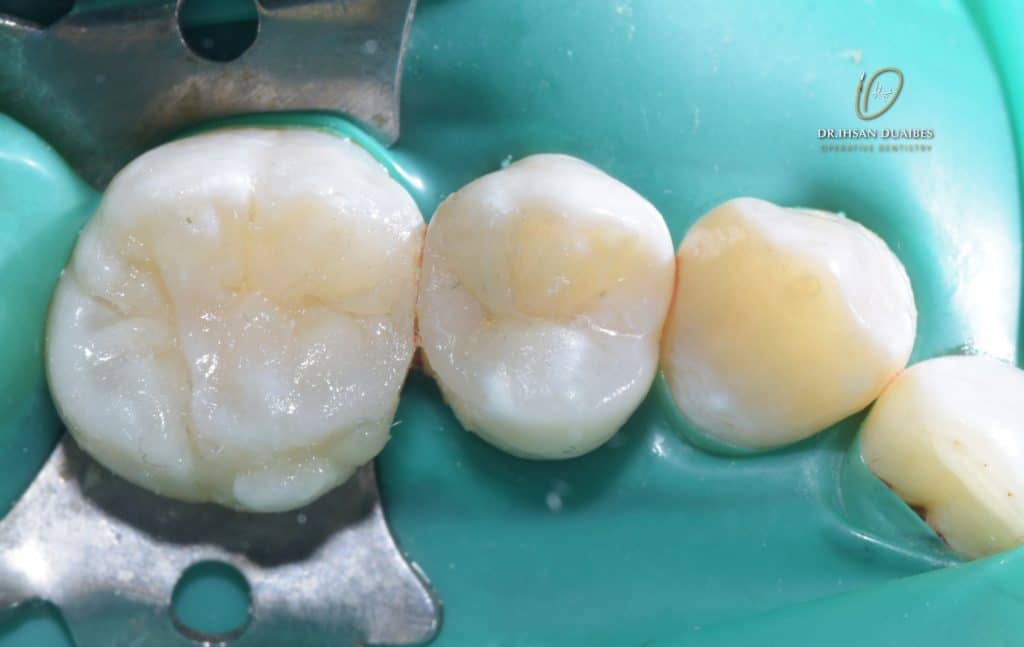

Molar restored

After occlusal check